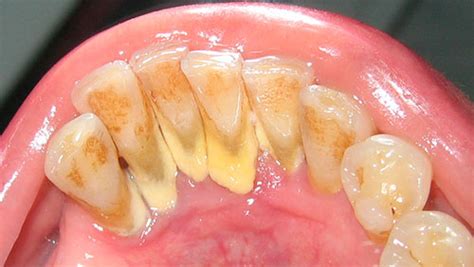

El sarro dental, también conocido como cálculo dental o tártaro, es la placa que no se ha eliminado y se ha endurecido y vuelto porosa a causa de los minerales de la saliva. Es decir, es la mineralización y calcificación de la placa dental, a la que se irán adhiriendo bacterias orales y otras sustancias, como la saliva o el calcio, formando una capa dura y amarillenta. En definitiva, el sarro es el empeoramiento y endurecimiento de la placa que no ha sido eliminada.

El sarro se distingue por su color, que puede ir de blanquecino a pardo. Aparece en la línea de las encías y, si no se elimina, continúa creciendo y calcificándose. Esta capa de suciedad también se puede acumular en el borde o debajo de las encías, llegando a irritar los tejidos gingivales.

El sarro está colonizado por las bacterias de la cavidad oral o placa bacteriana, responsable a su vez de muchas de las patologías de los dientes y encías.